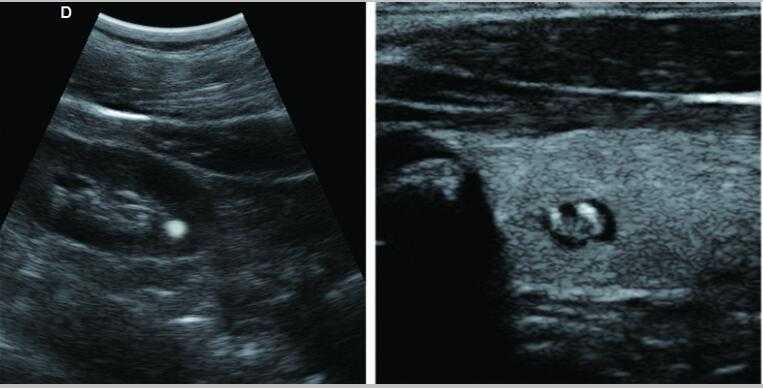

7.應用:腹部、婦科、產科、心臟、血管和小器官、泌尿科、肌肉骨骼、兒科等